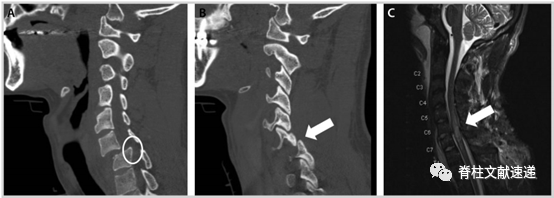

图注:图A、B为C6-7脱位的CT结果,图C为MRI的T2加权像结果显示以C6-C7为中心的外伤性脊髓损伤, C5至T1均存在不同程度的脊髓信号异常。

MRI能够准确的判断脊柱、脊髓损伤程度,特别是当CT提示脊髓、椎间盘等可能存在损伤或无法解释的神经系统检查时,MRI可以帮助我们早期诊断、估计预后(椎管内出血(> 1cm长)以及T2信号纵向改变> 3cm与预后不良有关,正常的MRI结果通常预示患者能够恢复正常)及制定治疗决策。